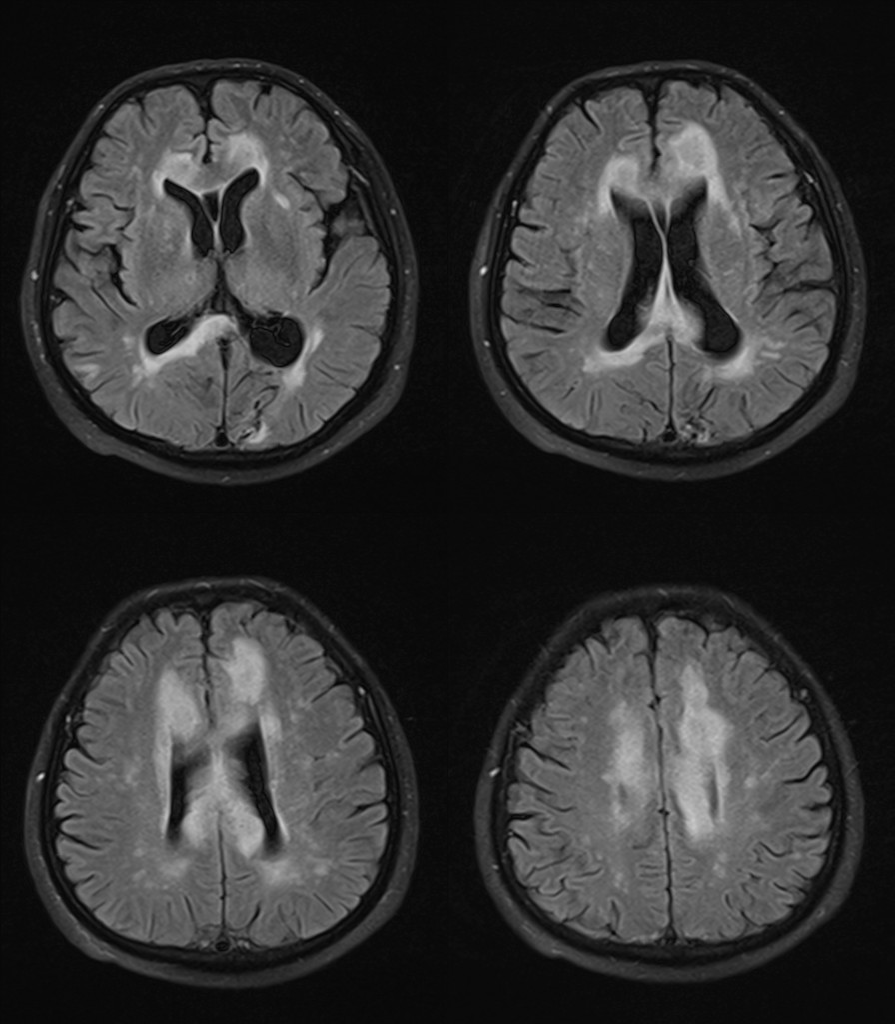

影像资料:

•急性期表现为胼胝体弥漫性肿胀,T1WI呈稍低信号,T2WI及FLAIR呈稍高信号,以矢状位观察最佳,可单独累及胼胝体压部或整个胼胝体,DWI呈高信号,ADC图呈低信号,部分患者可观察到脑室周围白质或内囊受累,少见皮层受累,表现为扩散受限,不强化和强化病例均可见到。如果增强扫描可见胼胝体有不同程度强化,呈小灶状或不规则斑片状,系血脑屏障破坏所致(如本例),本例患者处于急性期。

48岁,男性,长期饮酒过量20年,出现出现眩晕,胼胝体、侧脑室周围白质、内囊后肢对称性异常信号,扩散受限,诊断为原发性胼胝体变性急性期。

上排:原发性胼胝体变性急性期

下排:原发性胼胝体变性慢性期,表现为胼胝体萎缩、软化

急性期原发性胼胝体变性(胼胝体压部及体部病变,CT呈低密度,T1WI呈稍低信号,FLAIR呈稍高信号,扩散受限)向慢性期转变,慢性期胼胝体压部病灶出现坏死或囊变,FLAIR呈低信号